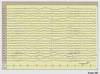

Normal awake EEG

Eyeblinks, posterior dominant rhythm

Normal EEG

The background activity is posteriorly dominant alpha rhythm at 9 to 9.5 Hz. This is normal waking occipital activity. The normal

occipital background rhythm disappears on eye opening which is shown in the EEG tracing.